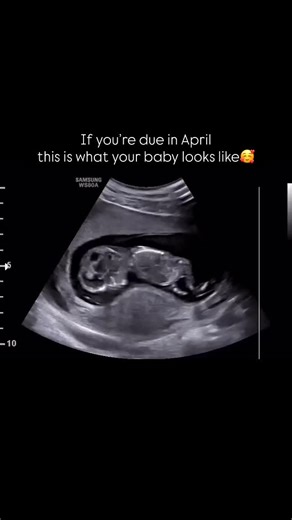

2D/3D-4D/5D HD Ultrasound on Instagram: "Where all the April ma

…